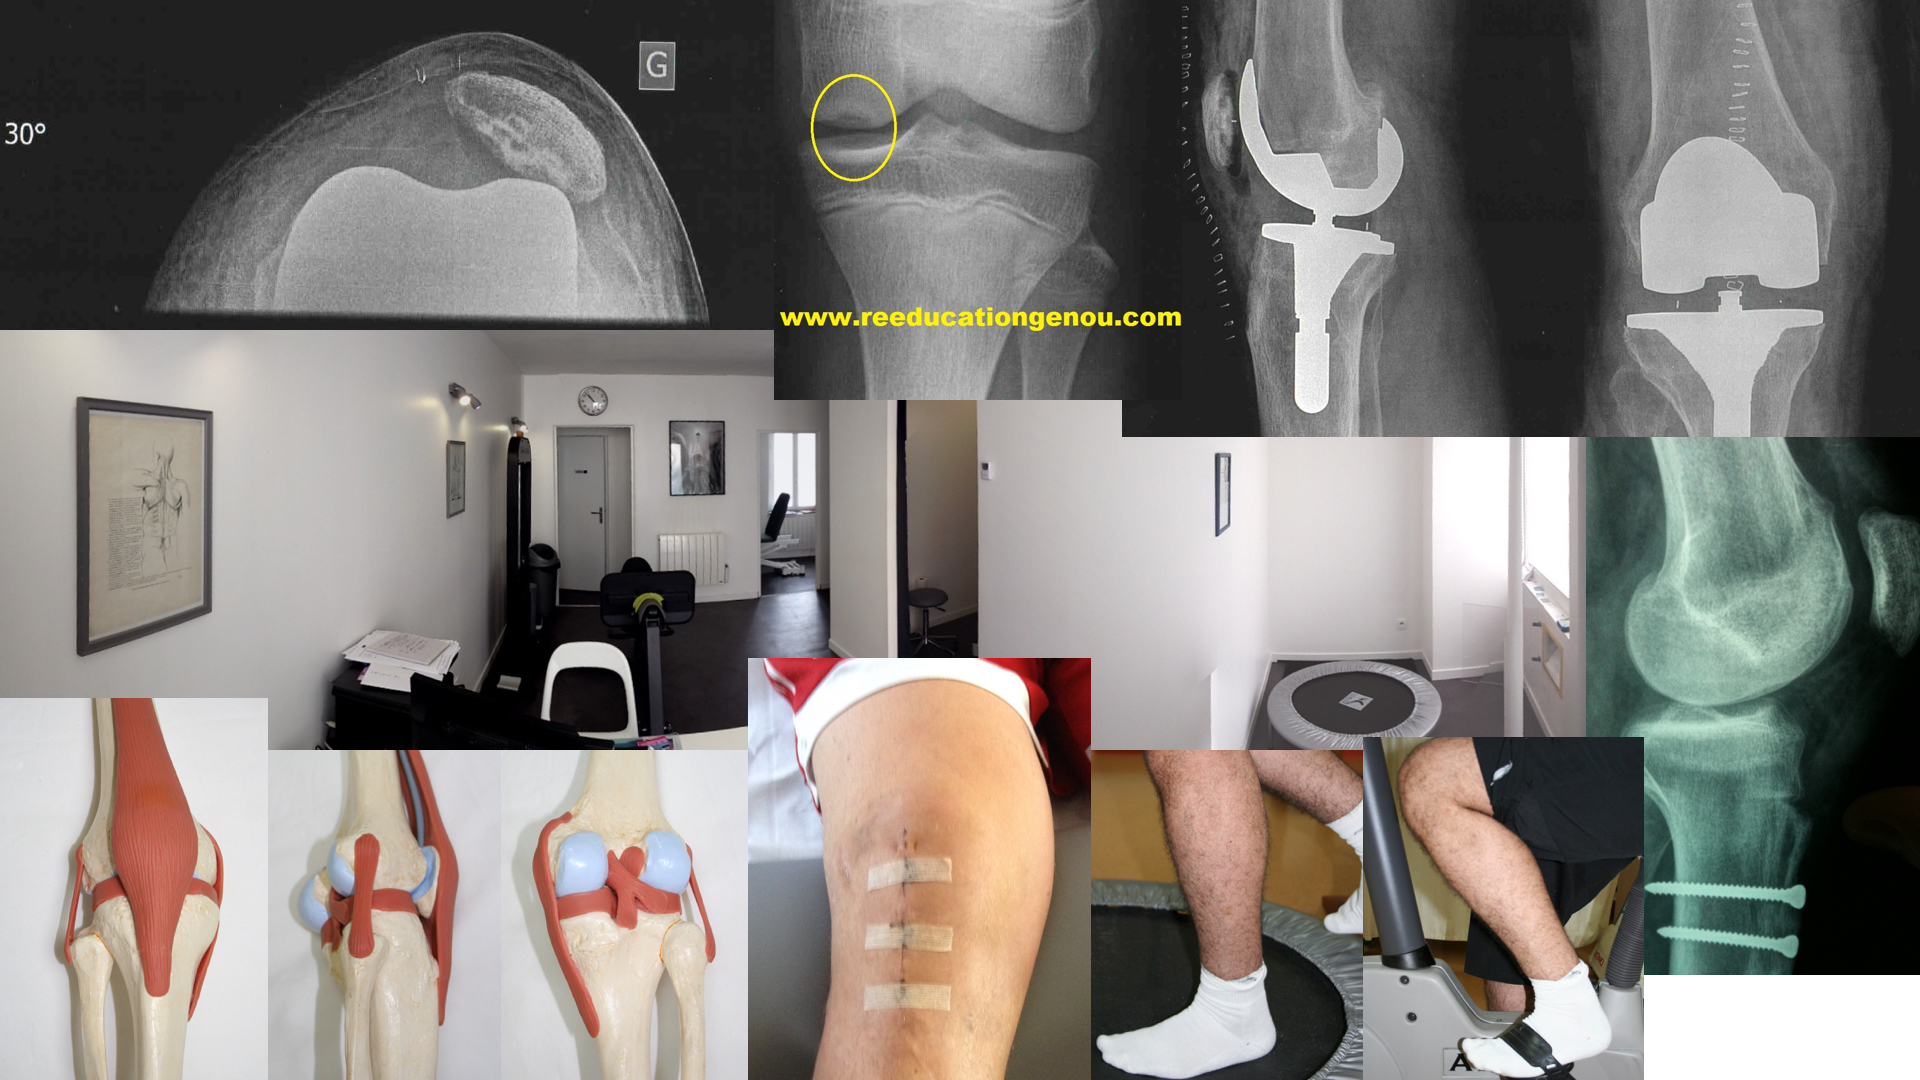

Les entorses du Ligament Croisé Postérieur

Elles sont rares et souvent traumatiques

elles font suite à un accident de la circulation comme le tibia du motard qui bute contre un pare choc...anecdotiquement une chute sur les genoux pliés qui va faire fortement reculer le tibia sous le femur.

Les conséquences d'une rupture du LCP non opéré

Il s'agit alors d'une instabilité postérieure avec à long terme une majoration de l'hyperextension signifiant l'usure du coin postérieur méniscal.

Souvent les patients consultent pour des douleurs de rotule...

En général la contraction isolée des ischios jambiers produit le recul du tibia (=tiroir postérieur) avec un avalement de la TTA

le creux sous la rotule est l'avalement de la TTA

= tiroir postérieur du aux ischios jambiers